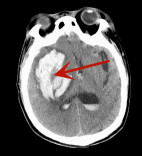

百岁老人命悬一线,医者仁心创造生命奇迹——新田县中医医院成功救治高龄急性硬膜下血肿并脑疝患者